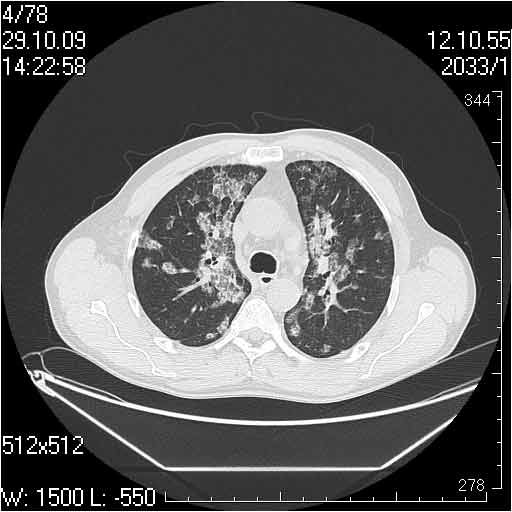

Случай №3

Женщина 51 год

Случай 3:смешанные изменения; подходят для интерстициальной пневмонии, тактика аналогична случаю 1.